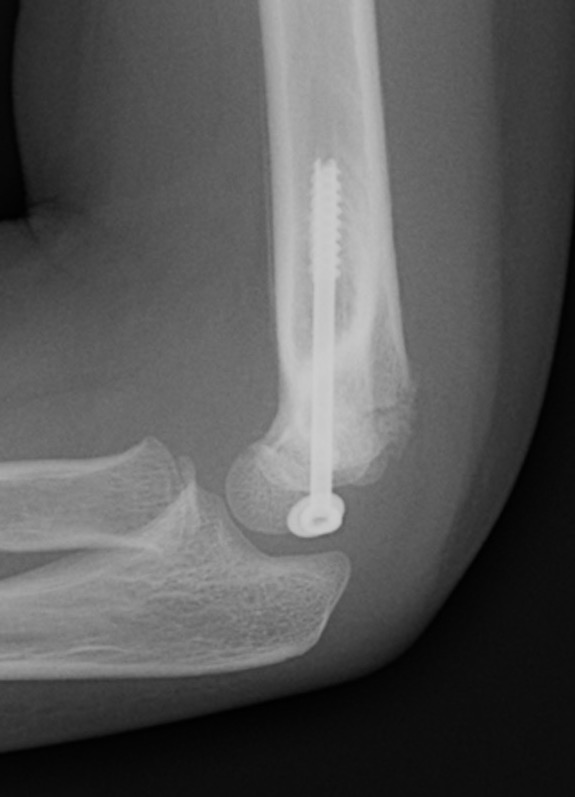

Open reduction of displaced lateral condyle in left elbow

Post op

- very real risk of non union

- elbow in POP for 6 weeks

- don't remove K wires until obvious union at 6 weeks